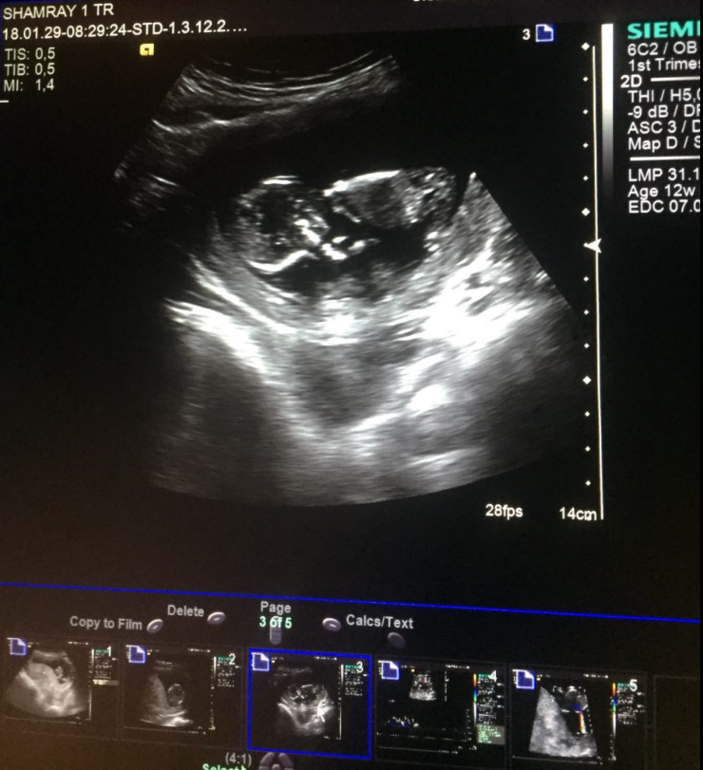

но на завтра назначена встреча с врачом, там осмотр, ктг, узи и все такое. если шейка готова, то будут стимулировать. на сроке 41 неделя (только начало 41 недели!)